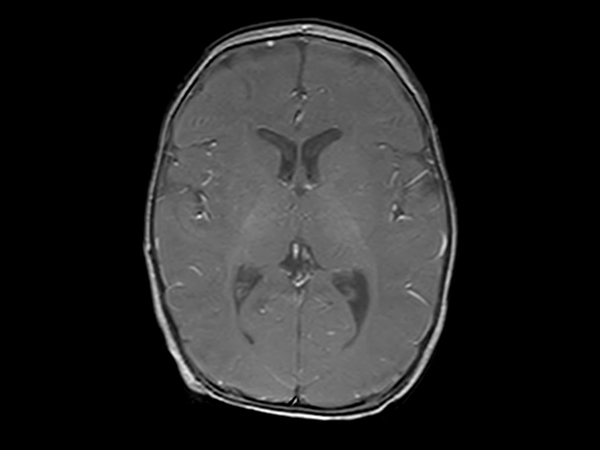

Axial SWIp